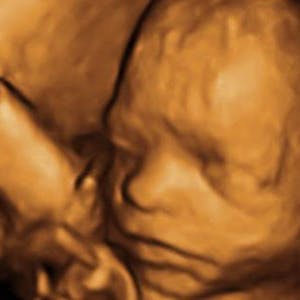

Gravid

Vi gør en dyd ud af at klæde dig godt på både før, under og efter din graviditet. Vi ved, at der kan komme mange spørgsmål til din graviditet, fødsel, amning, din babys udvikling og mange flere emner, derfor har vi samlet guides, tips & tricks samt læsernes egne fortællinger i dette gravid univers.